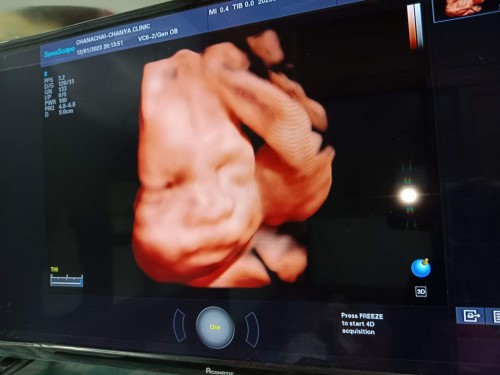

มาแชร์รูปเจ้าตัวน้อย 24วีค ค่ะ 💖

แม่ๆซาว 4มิติ ตอนอายุครรภ์เท่าไหร่บ้างคะ แล้วช่วงไหนที่เหมาะกับการซาว4มิติที่สุดคะ#ท้องแรกคะ #คุณแม่ๆช่วยแนะนำหน่อยค่ะ

บ้านนี้24วีคน้ำหนัก719ค่ะ

800 ค่ะ อันนี้ ยังไม่ใช่ซาว4มิตินะคะ แม่ แค่3 มิติจ้า